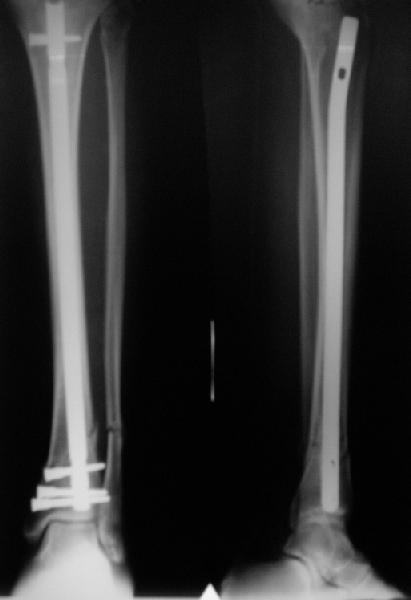

A typical case is attached, also an image with intra-op reduction obtained by a small wire distractor, in the moment of insertion a Poller wire in AP direction. Fixation by a SIGN nail. Despite the fibula was not fixed healing was obtained with the unchanged alignment.

[ Ответить ]